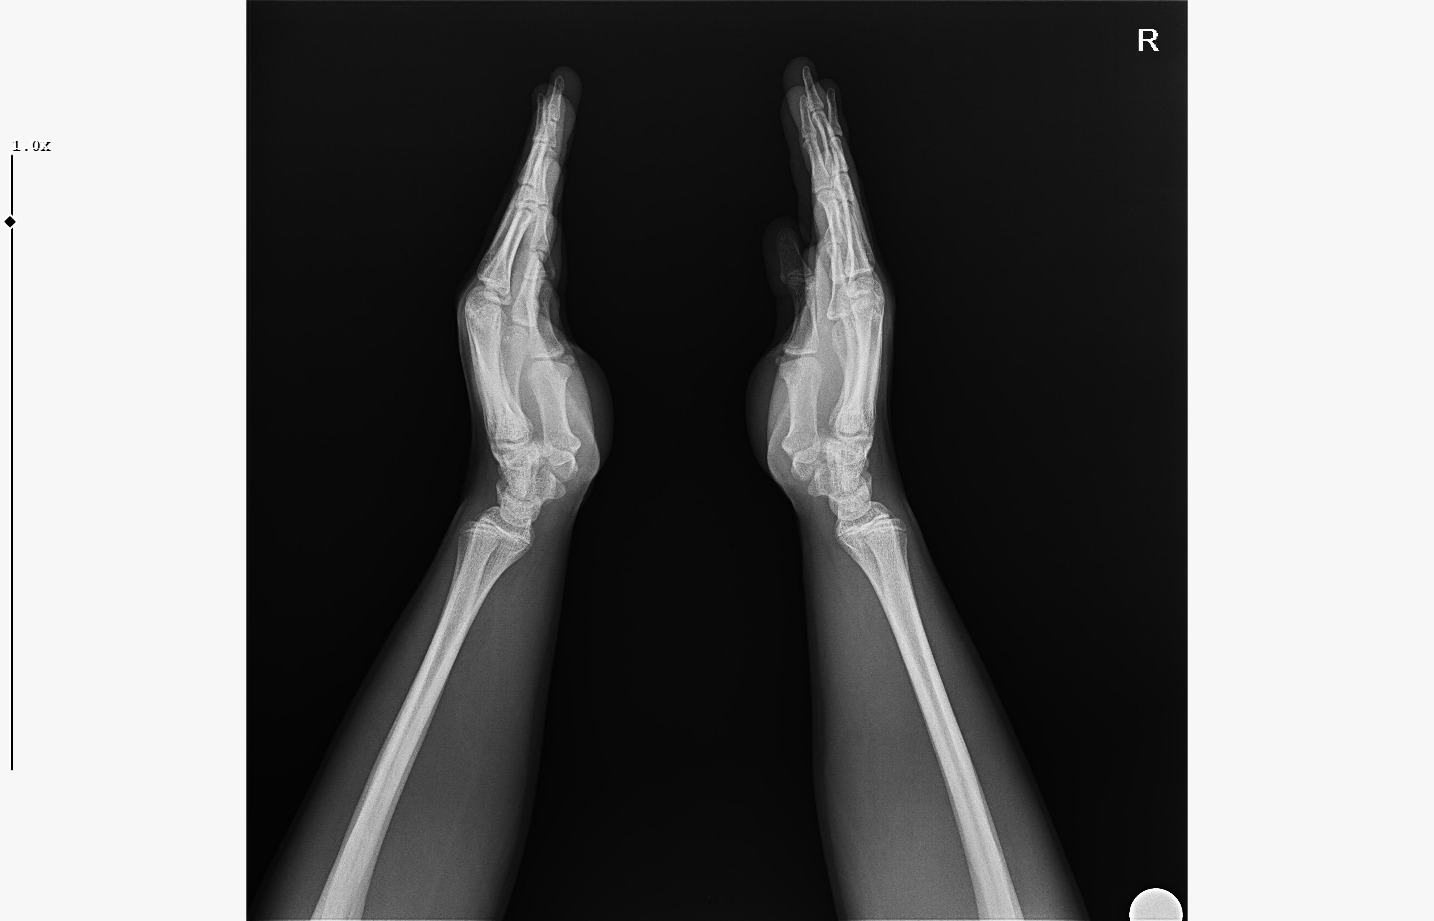

doktor bi sik bilmiyodur büyük ihtimalle plakları buraya at biz bakak

bide bir sekilde hgh temin et babandan kısasın uzama olasılığın çok daha fazla gh ile,şuan ona paran yoksa da biriktirmeye başla aromasin kullan

IMG 5959

röntgeni atar mısın?

böyle ne diyorsun yaşım genc bu arada

Attachments

• WhatsApp Image 2026-01-07 at 00.31.08 (4).jpeg

WhatsApp Image 2026-01-07 at 00.31.08 (4).jpeg

161.8 KB · Views: 0

• WhatsApp Image 2026-01-07 at 00.31.08 (3).jpeg

WhatsApp Image 2026-01-07 at 00.31.08 (3).jpeg

104.8 KB · Views: 0

• WhatsApp Image 2026-01-07 at 00.31.08 (1).jpeg

WhatsApp Image 2026-01-07 at 00.31.08 (1).jpeg

140.5 KB · Views: 0

• WhatsApp Image 2026-01-07 at 00.31.08.jpeg

WhatsApp Image 2026-01-07 at 00.31.08.jpeg

138.6 KB · Views: 0

bilmiyo zaten,ki el plakları boy ile neredeyse hicbirsey göstermiyo bile ama tr de hangi doktora gidersen git %95inden fazlası el plağına bakcak ona göre yorum yapcak

kapanmaya baslamıs ama cok yakın degil

kemik yaşın 15 gibi 15'e çok yakın

anne baba boyun ve yaşını bilmiyorum sadece bu bilgilerle 171-175 arası diye tahmin ediyorum röntgen ile.

normalde anne babana göre 171-176 olman gerek zaten. kemik yaşın ve şuanki boyun ile yapılacak tahmin anne baban ile yapılabilecek tahminle nerdeyse birebir aynı yani büyük ihtimal o civarlar olursun bence